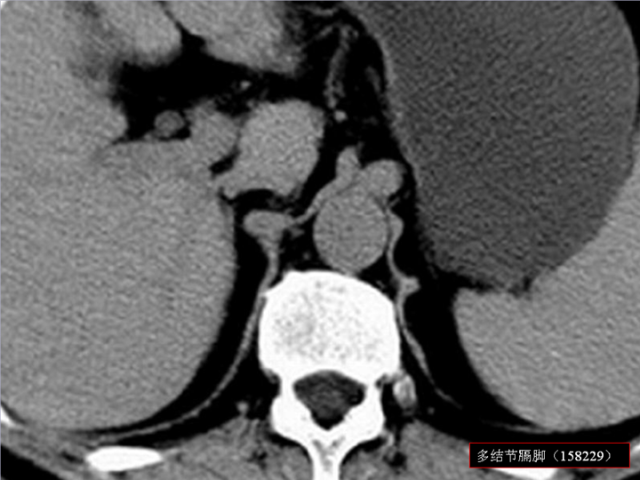

膈肌角解剖及常见变异

作者:王俭 上海长征医院